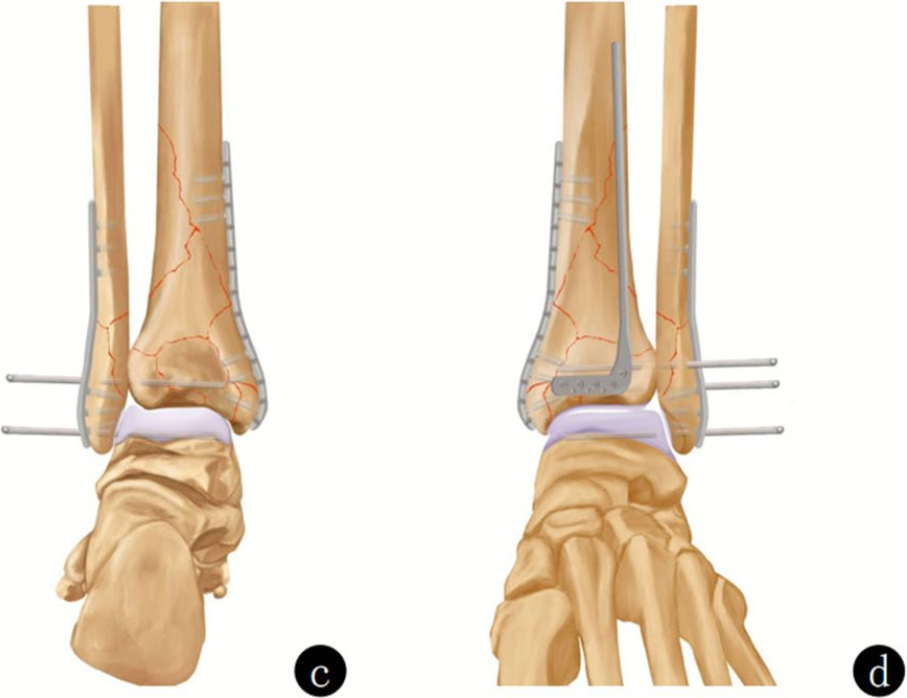

图a、b. 术前X线片显示Pilon骨折(AO 43-C3)。由于干骺端存在粉碎区域,关节骨折块与完整的骨干之间缺乏参照;c、d. 通过 “扩大外侧入路” 联合小的内侧入路,首先对关节骨块进行解剖复位,从而将C型骨折转化为A型骨折。随后,对骨折进行功能对位并固定到骨干上。